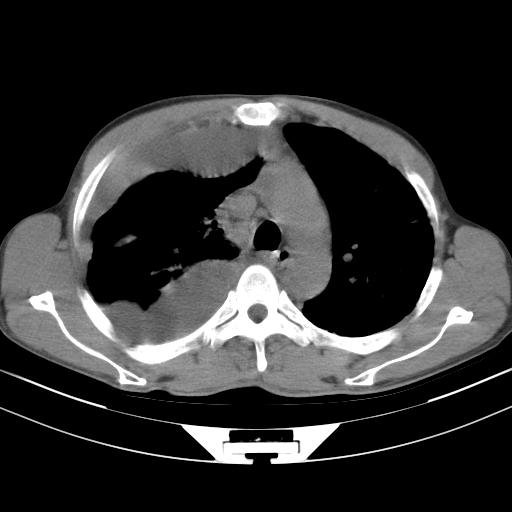

男性,44岁,结核病史多年。现胸闷气短,咳嗽,偶咳血。

右侧胸腔积液

右肺下叶不张

双肺多发结节影最分空洞形成考虑占位不除外结核

双肺陈旧性病变

1、右侧大量胸腔积液伴右肺压缩性膨胀不全,建议抽液治疗后复查 2、两肺继发性tb伴空洞形成。

1)两肺继发性肺结核伴空洞形成,左肺多发性结核球。2)右侧大量胸腔积液伴右肺部分膨胀不全。3)纵隔淋巴结肿大。